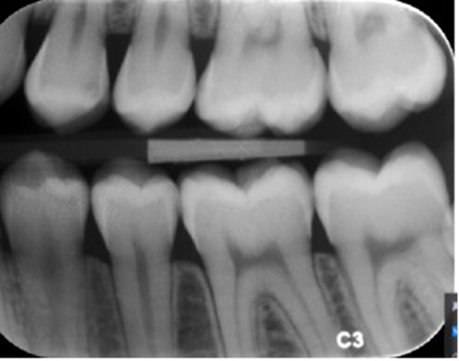

Vurder den optiske densitet på denne fosforplade.

Passende/god

emalje tydeligt radiopak

dentin kan skelnes fra emalje

trabekulært knoglemønster synligt

pulparum radiolucent

billedet hverken for mørkt eller for lyst